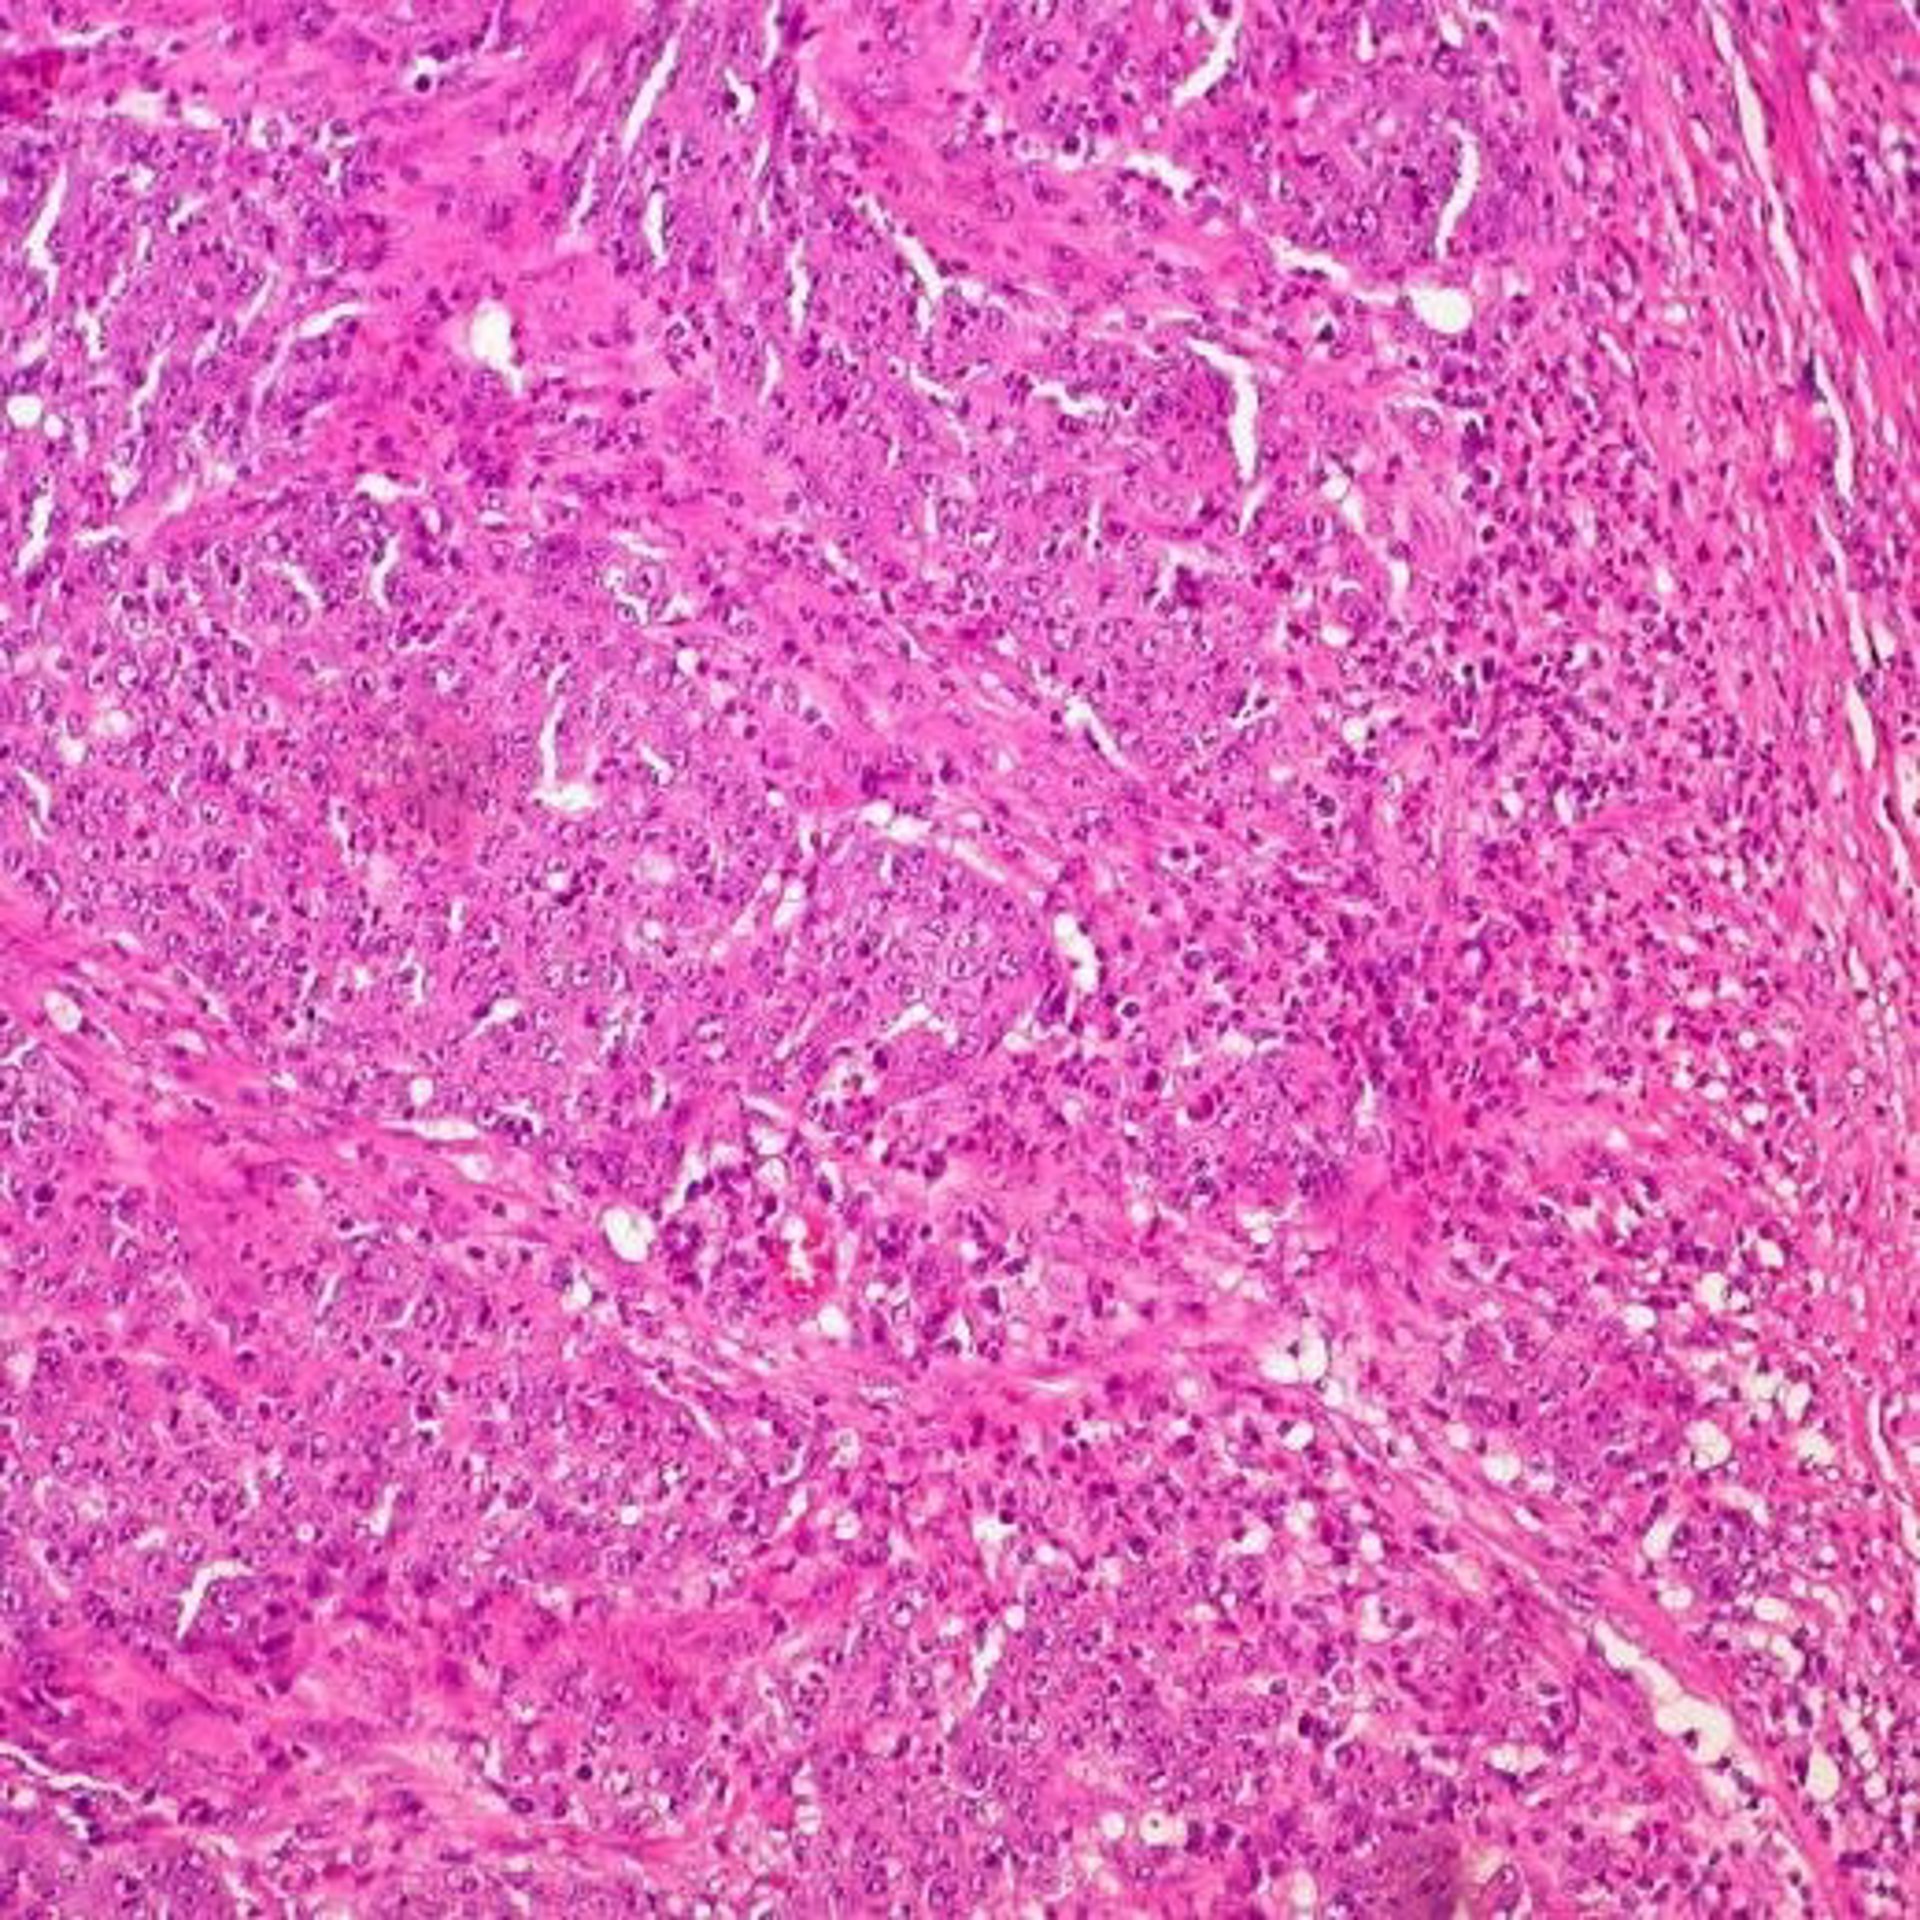

Cáncer de colon